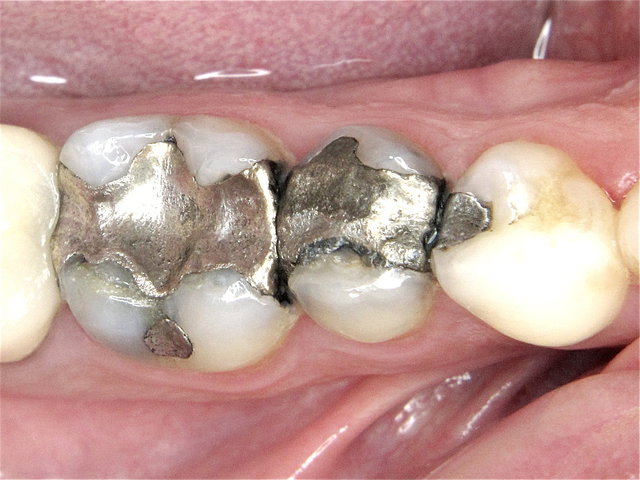

Alte Amalgam-Füllungen mit Sekundärkaries ...

Composit-Füllungen by CLINICDENT ✓